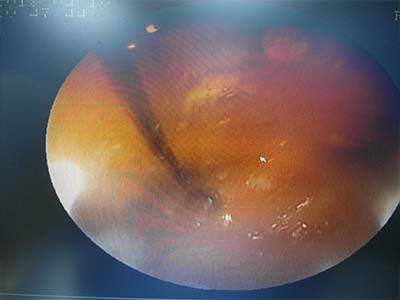

內視鏡可以看到針卡在胃部